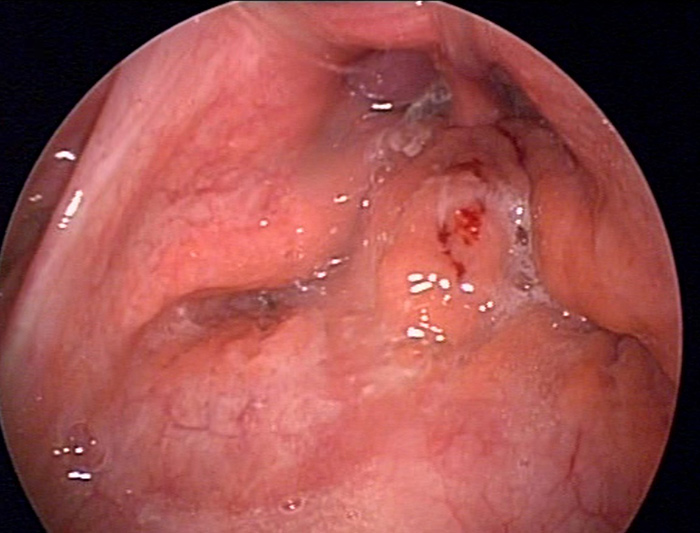

É indicada para alguns pacientes com amigdalites de repetição ou aumento das amígdalas. A cirurgia é realizada com anestesia geral, em centro cirúrgico hospitalar, sem cortes externo, por dentro da boca. Dura cerca de 1 hora e normalmente a alta é no mesmo dia. Pode ser necessário passar a noite após a cirurgia se ocorrer sangramento excessivo, muita dor ou pouca ingestão de líquidos.

Uma placa branca de cicatrização ocorre após a cirurgia no local onde estavam as amígdalas. NÃO É INFECÇÃO!!!